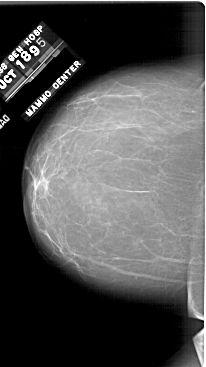

A_1748_1.RIGHT_CC

RIGHT_CC LINES 6346 PIXELS_PER_LINE 3496 BITS_PER_PIXEL 12 RESOLUTION 43.5 OVERLAY

FILE: A_1748_1.RIGHT_CC.OVERLAY

TOTAL_ABNORMALITIES 1

ABNORMALITY 1

LESION_TYPE MASS SHAPE LOBULATED MARGINS CIRCUMSCRIBED

ASSESSMENT 3

SUBTLETY 3

PATHOLOGY BENIGN

TOTAL_OUTLINES 1

BOUNDARY